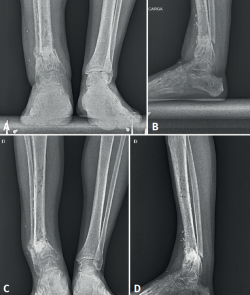

Se trata de un varón de 39 años sin antecedentes patológicos de interés que tras una caída desde altura sufre fracturas cerradas de pilón tibial y de peroné suprasindesmal (Figura 1). Presenta en el momento gran tumefacción generalizada del tobillo sin presentar flictenas ni soluciones de continuidad en la piel. Se realiza una fijación externa temporal con un sistema Hoffmann 3, que 10 días después se recambia por una fijación interna con placas y tornillos (Figura 2).

Figura 1. Radiografía. Fractura conminuta del pilón tibial derecho y fractura del peroné suprasindesmal ipsilateral. Estabilizada con férula suropédica.

Figura 4. Radiografías A y B: deformidad del tobillo un mes tras la retirada del fijador externo; C y D: 5 meses tras la retirada.